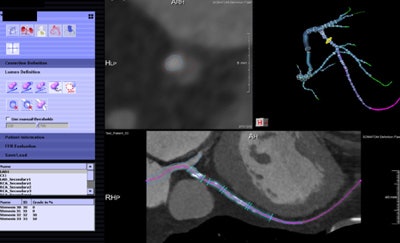

The new algorithm processes the data in several steps, beginning with automatic data tracking, then segmentation of the vessels, and finally creating a 3D coronary artery model. The segmentation process takes about 16 minutes on a laptop computer, calculation another 15 minutes per dataset, Nieman said. Similar to the original FFR-CT algorithm, the user must know the left-ventriuclar mass to calculate the blood flow, he said.